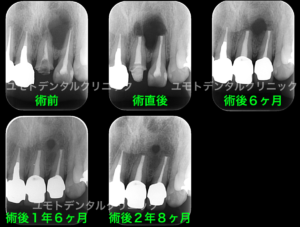

本症例においては透過像の原因歯は左上1番と診断しておりますが、左上2番の症状も該当歯とは別に確認されたため、左上1番の再根管治療後に両歯を外科的歯内療法を行っております。

根管治療前、外科的歯内療法直後、術後6ヶ月

予後観察(検診)時

本ケースにおいては唇側から口蓋側に交通する骨欠損を生じていたため、骨の完全な再生ではなく瘢痕治癒という形態を最終的なゴールと定めさせていただきました。